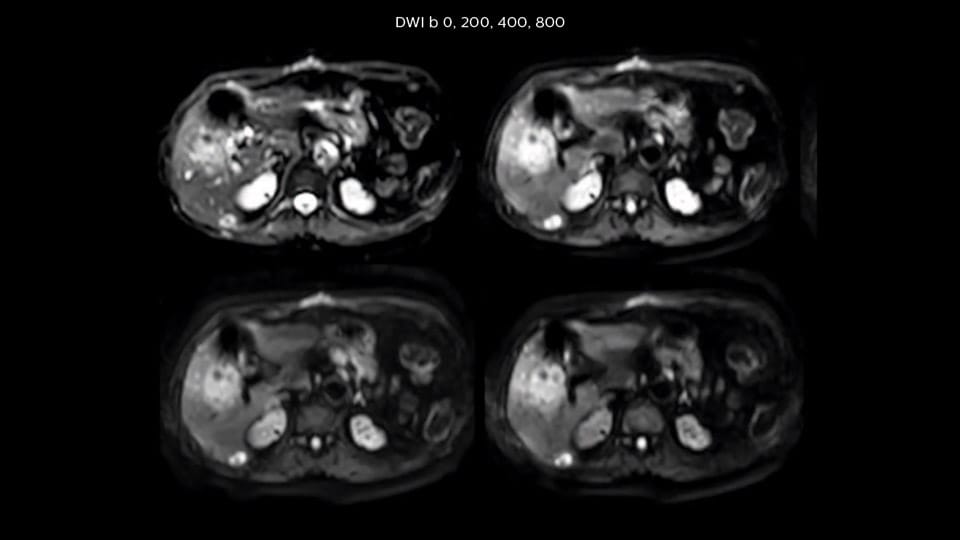

In this example the image quality of the MultiVane XD images is evidently better than in the images without MultiVane XD. Ingenia 1.5T with dS Torso coil solution.

“Our liver exams are quite fast,” says Dr. Baumann. “If the patient tolerates it, we use an arms-up position to reduce the FOV and speed up the exam with dS SENSE.” “We acquire one transversal high resolution T2-weighted sequence with 3 mm slice thickness, for example for pancreas or liver lesions. Then we also add a T2 fat suppressed MultiVane XD SPIR sequence. We perform these two routinely in our liver imaging. We use high dS SENSE factors to significantly shorten scan times to 2-4 minutes, which can improve our protocol; it’s a very robust scan.” “We include mDIXON for the dynamic sequences because of the robust and homogeneous fat suppression we get with that. We had been using eTHRIVE, but we are now quite happy with mDIXON. Sometimes we use a medication to calm the bowels, to further improve the image quality.”